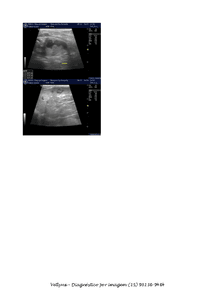

A Manu está com câncer na bexiga. Atualmente o câncer está num tamanho que ocupa quase toda a bexiga. Ela mal dorme pois precisa levantar toda hora para fazer xixi, e quando faz, sai sangue.